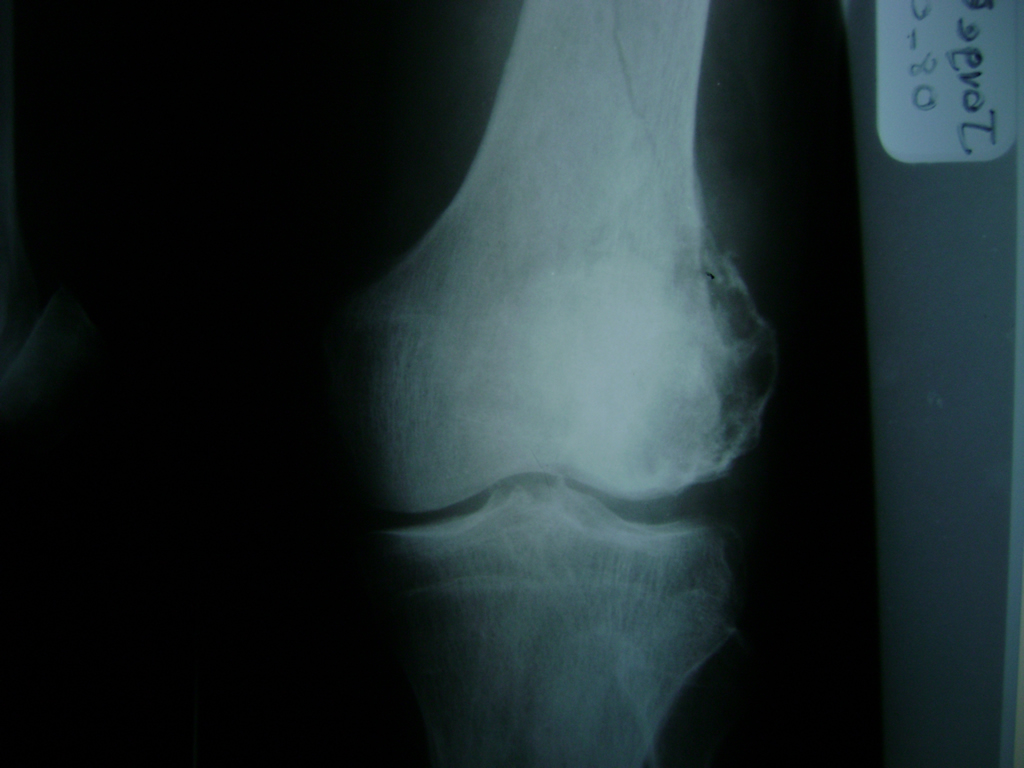

Húmero - Rodilla